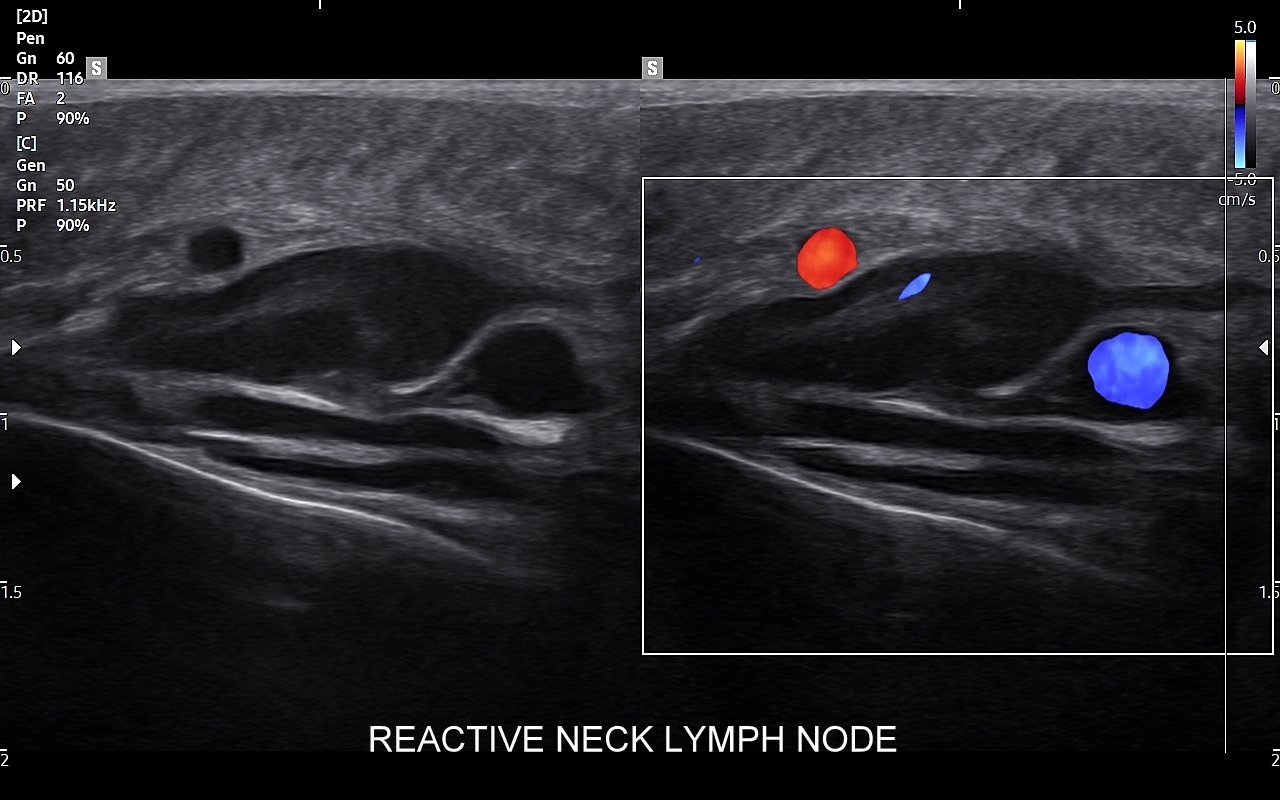

Badanie USG jest podstawową metodą obrazowania węzłów chłonnych. W jego trakcie ocenia się nie tylko wielkość węzłów, lecz także ich kształt, proporcje wymiarów, morfologię, czyli wygląd zewnętrzny oraz strukturę wewnętrzną, ich unaczynienie, spoistość, a także tkanki otoczające. W trakcie interpretacji badania pod uwagę bierze się również zbierany od pacjenta wywiad chorobowy oraz wyniki innych badań obrazowych i laboratoryjnych takich jak morfologia, OB, CRP, żelazo, ferrytyna, TIBC, innych parametrów infekcyjnych, a także onkologicznych. Ultrasonografia węzłów chłonnych jest procedurą bezpieczną i dokładną. W Pracowni dr Szczepańskiego węzły chłonne oceniane są nowoczesną metodą MPUS (multiparametryczne badanie USG), w szczególności z zastosowaniem trybów mikrounaczynienia i elastografii.

Do powiększenia węzłów chłonnych szyi, stanu określanego jako limfadenopatia, dochodzi najczęściej w przebiegu chorób zakaźnych górnych dróg oddechowych, wirusowych i bakteryjnych. Inne przykłady przyczyn limfadenopatii szyjnej obejmują ropne choroby zębów, migdałków i zatok przynosowych; odczyny w chorobach autoimmunologicznych, np. w chorobie Hashimoto i Sjögrena; a także rozrostowe schorzenia układu hematologicznego (białaczki i chłoniaki) i choroby nowotworowe jak np. rak tarczycy, krtani, migdałka, czy języka. Należy mieć na uwadze, iż w przypadku podejrzenia chorób układu krwiotwórczego oraz mononukleozy zakaźnej, oprócz węzłów chłonnych, niezbędne jest również badanie USG wątroby i śledziony. W części przypadków, gdy podejrzewa się możliwość choroby nowotworowej lub w celu jej wykluczenia, lekarz może zalecić rozszerzenie diagnostyki obrazowej na inne obszary ciała.